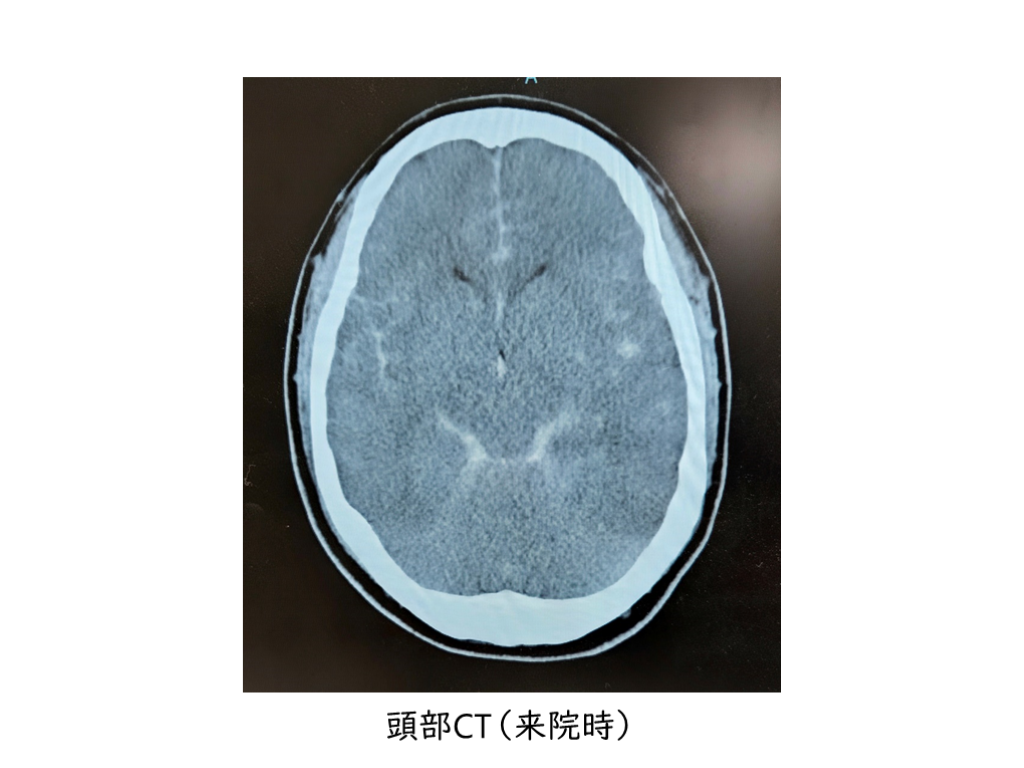

症例呈示 30歳代男性 バイク走行中に乗用車と衝突した。救急隊接触時、CPA(心電図波形:心静止)。病着後、9分で自己心拍再開。 既往歴:特記すべきことなし JCS:III-300, GCS:E1VTM1, 瞳孔:5mm/5mm, 対光反射なし ICU入室後、体温管理療法開始 低血圧のため、昇圧剤(ノルアドレナリン, バゾプレッシン)を要する状態

#8.

頭部CT(来院時)

#9.

いやあ、予後厳しそう。臓器提供についての話をしたほうがいいのかなあ。どういうタイミングで、どんなふうに話したらいいんだろう。経験ないんだよなあ。 主治医(救急科)